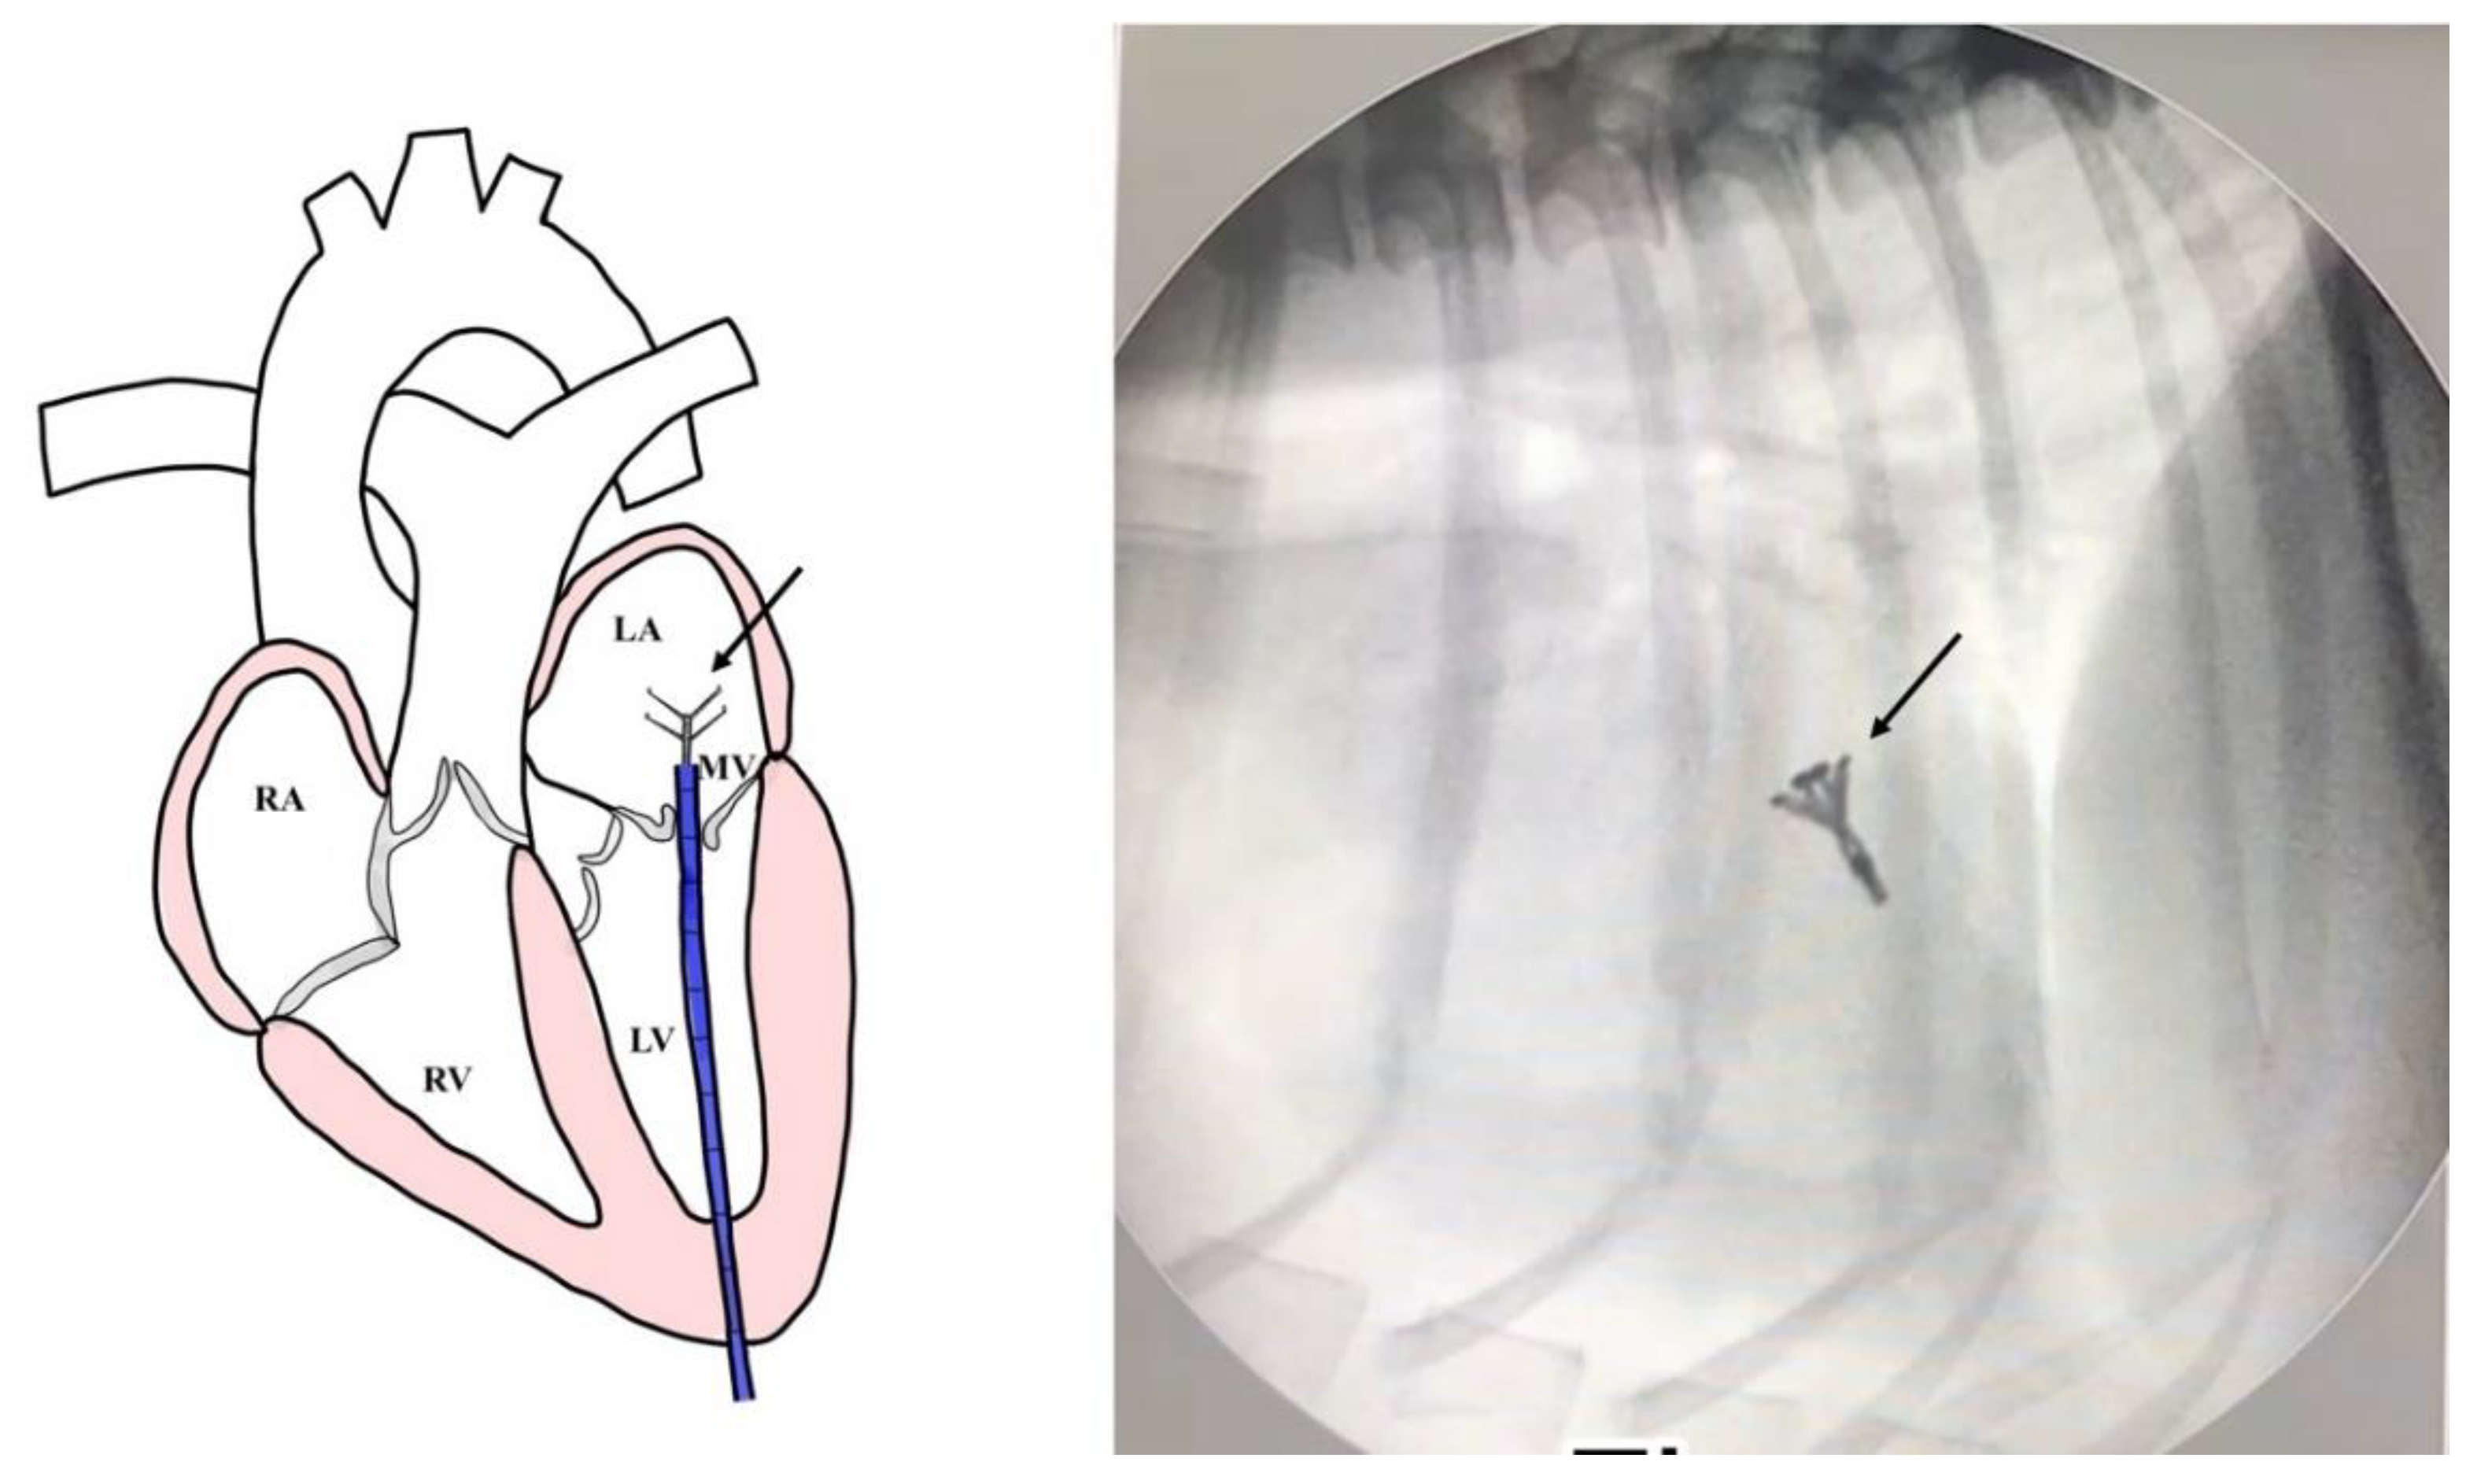

Surgical Intervention